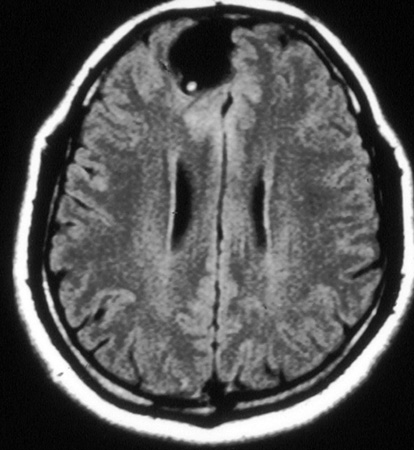

RNM cranioencefálica/da coluna

Exame

A neuroimagem é a base do diagnóstico para a neurocisticercose. A RNM é superior à TC na identificação de cistos extraparenquimatosos e lesões da fossa posterior, mas a TC é melhor na visualização de cistos calcificados.[39] A RNM também pode revelar o escólex que, geralmente, não é visível em TCs. Idealmente, ambos os testes devem ser considerados.

Achados específicos dependem da localização dos cistos (consulte tomografia computadorizada do cérebro, acima).[33][40]

Todos os pacientes com doença subaracnoide devem fazer uma RNM da coluna.[33][Figure caption and citation for the preceding image starts]: Estádio cístico - neurocisticercose: ressonância nuclear magnética (RNM) mostrando lesão cística no lobo frontal; é possível observar um escólex no interior do cistoDo acervo da Dra. Christina Coyle e do Dr. Maheen Saeed; usado com permissão [Citation ends].

[Figure caption and citation for the preceding image starts]: Estádio granular - neurocisticercose: RNM mostrando lesão com realce sem edema perilesionalDo acervo da Dra. Christina Coyle e do Dr. Maheen Saeed; usado com permissão [Citation ends].

[Figure caption and citation for the preceding image starts]: Estádio calcificado - neurocisticercose: RNM de várias lesões calcificadas em um paciente com neurocisticercoseDo acervo da Dra. Christina Coyle e do Dr. Maheen Saeed; usado com permissão [Citation ends].

Resultado

escólex de tênia de cisticercos extraparenquimatosos; achados específicos dependem da localização dos cistos